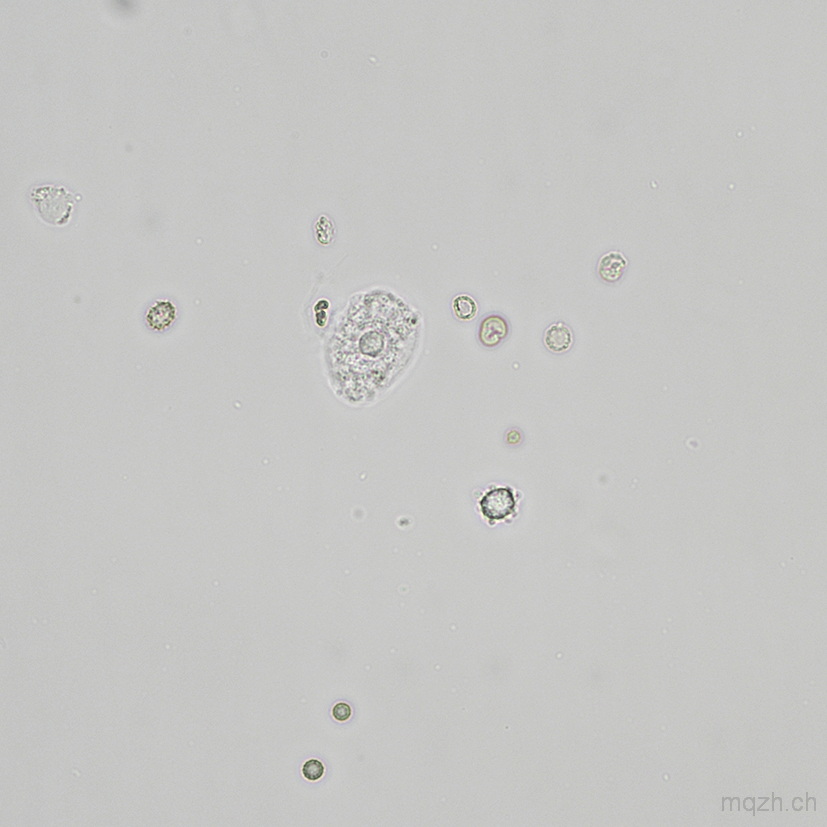

MQ 2025-4 Urinary Sediment U4